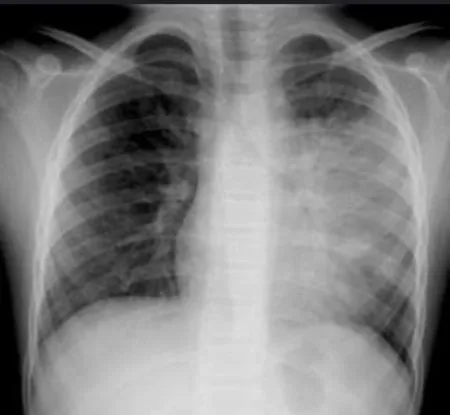

🩸Çin ve buradan yayılan, beyaz akciğer zatürresi denilen pnömoni.⭐️Hangi patojenlerin neden olduğu belli, hepsini yazacağım.…